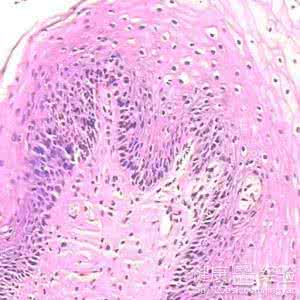

宫颈HPV感染多为亚临床型,单靠肉眼识别将有大部分病人被漏诊,有资料显示宫颈湿疣的临床漏诊率达85%,这成为复发和蔓延的原因,并且宫颈HPV感染有发展至宫颈癌的危险性,早期彻底治疗有助于降低宫颈癌的发生。应用阴道镜早期可发现宫颈部的异型上皮、异型血管以及早期癌变,并准确地选择可疑部位作活体组织检查。有调查显示阴道镜和病理诊断符合率为99%。

(3)宫颈尖锐湿疣是由病毒感染所致,可引起妇女大小阴唇、阴道口、尿道口、阴道壁等处生长形态各异的疣体。同时该病毒还可感染宫颈部而引起宫颈炎,对此人们没有足够的重视,很多病人只注重外阴部明显疣体的治疗,而忽视病毒侵犯宫颈部形成的隐患。

(4)有资料显示宫颈湿疣的临床漏诊率达85%,这成为复发和蔓延的原因,并且宫颈HPV感染有发展至宫颈癌的危险性。早期彻底治疗尖锐湿疣有助于降低宫颈癌的发生。应用阴道镜早期可发现宫颈部的异型上皮、异型血管以及早期癌变,并准确地选择可疑部位作活体组织检查。